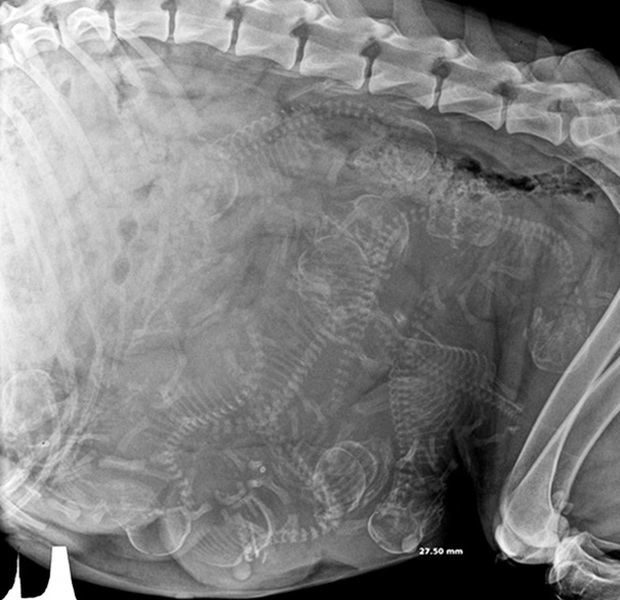

Trông có vẻ như các bé cún rất đông mà bụng chó mẹ thì lại chật hẹp. Thời gian thai của những chú cún hình thành và làm tổ ở sừng tử cung cho tới khi ra đời là khoảng 58 - 68 ngày (trung bình là 9 tuần). Những chú chó càng ít thai (dưới 4 con) thì thời gian mang thai càng dài.

Cận cảnh hình chụp X-quang một cô mèo đang mang thai và loạt ảnh động vật mang bầu khiến người xem rùng mình nhưng rồi thấy đẹp khó tả - Ảnh 3.